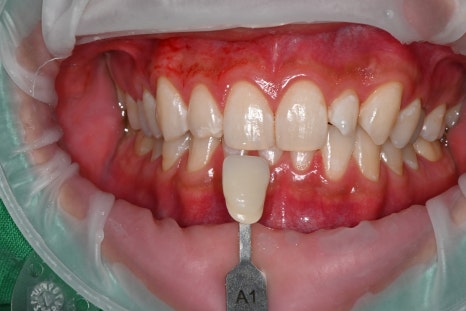

< 미백 전 A3 > 미백 후 A1 >

미백 전에는 치아 색이 A3 톤으로 다소 어두웠고,

미백 후에는 확실히 밝아졌습니다.

이 과정이 중요한 이유는,

오브제로 라미네이트의 색을

인접 치아와 자연스럽게 맞추기 위해서입니다.